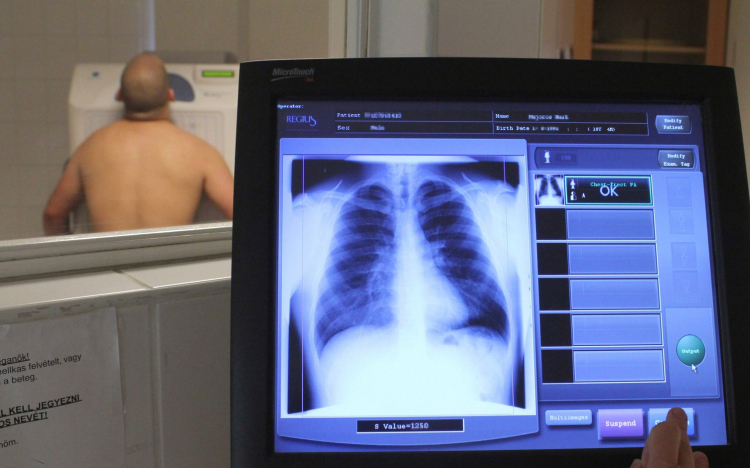

Egyre nő hazánkban a tüdőbetegek száma: idült légzőszervi betegségben, azaz COPD-ben félmillióan szenvednek.

A tüdőbetegségek között is folyamatosan nő a krónikus obstruktív légúti betegségek (COPD), az alsó légutak tartós beszűkülésével járó kórképek száma.

A konferencián elhangzott: a TBC-s betegek száma egyre csökken, hazánk az alacsonyan fertőzött fejlett országok közé tartozik ebből a szempontból, ám a COPD-s és asztmás betegek száma egyre növekszik, mint ahogyan a tüdődaganatban szenvedők száma is.

A hazai tüdőgyógyászati fekvőbeteg osztályokon a páciensek 60-70 százaléka daganatos beteg. A legnagyobb gond, hogy kétharmaduknál későn fedezzük fel a betegséget, hiszen a korai stádiumban nem okoz panaszt.

Jelenleg 22 ezer beteg van, ám számuk évente csaknem annyival nő, mint ahányat elveszítünk. A betegség öt éves túlélési aránya jelenleg 10-15 százalék – ismertette Szilasi Mária, a Debreceni Egyetem Tüdőgyógyászati Klinikájának igazgatója.

Kovács Gábor elmondta: napjainkban csak az USA néhány államában végzik CT-vel a tüdőrákszűrést, ám a világon mindenhol keresik ennek költséghatékony módját, amellyel a betegség a korai stádiumában is felismerhető lenne.